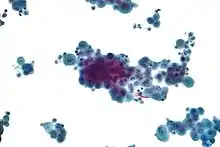

Biopsy

Generally, a biopsy is needed to confirm a diagnosis of malignant mesothelioma. A doctor removes a sample of tissue for examination under a microscope by a pathologist. A biopsy may be done in different ways, depending on where the abnormal area is located. If the cancer is in the chest, the doctor may perform a thoracoscopy. In this procedure, the doctor makes a small cut through the chest wall and puts a thin, lighted tube called a thoracoscope into the chest between two ribs. Thoracoscopy allows the doctor to look inside the chest and obtain tissue samples. Alternatively, the cardiothoracic surgeon might directly open the chest (thoracotomy). If the cancer is in the abdomen, the doctor may perform a laparoscopy. To obtain tissue for examination, the doctor makes a small incision in the abdomen and inserts a special instrument into the abdominal cavity. If these procedures do not yield enough tissue, an open surgical procedure may be necessary.

Immunochemistry

Immunohistochemical studies play an important role for the pathologist in differentiating malignant mesothelioma from neoplastic mimics, such as breast or lung cancer that has metastasized to the pleura. There are numerous tests and panels available, but no single test is perfect for distinguishing mesothelioma from carcinoma or even benign versus malignant. The positive markers indicate that mesothelioma is present; if other markers are positive it may indicate another type of cancer, such as breast or lung adenocarcinoma. Calretinin is a particularly important marker in distinguishing mesothelioma from metastatic breast or lung cancer.[12]